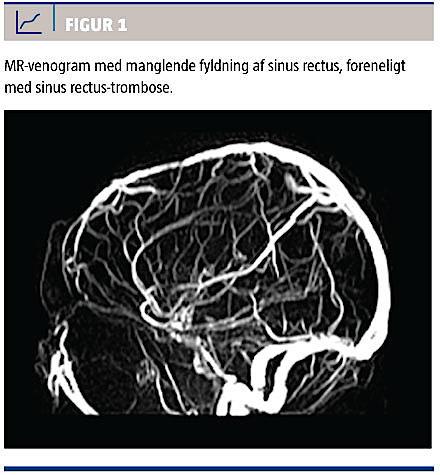

sinus sagittalis superior (såkaldt empty delta sign) ofte ses og i så fald være udtryk for en trombose i denne sinus. Diagnosen stilles dog bedst ved en CT af hjernen med angiosekvenser eller en MR-skanning af hjernen med venografi, hvor man direkte ser de lukkede vener (Figur 1) samt eventuelle blødninger og infarkter (Figur 2). Forandringer i thalamus er særligt kritiske, da de er tegn på manglende afløb fra de centrale dele af hjernen. Man skal være opmærksom på, at hypoplasi eller aplasi af f.eks. sinus transversus kan tage sig ud som sinustrombose på et MR-venogram [2]. Måling af en normal D-dimer kan ikke anvendes til udelukkelse af CVST [6].